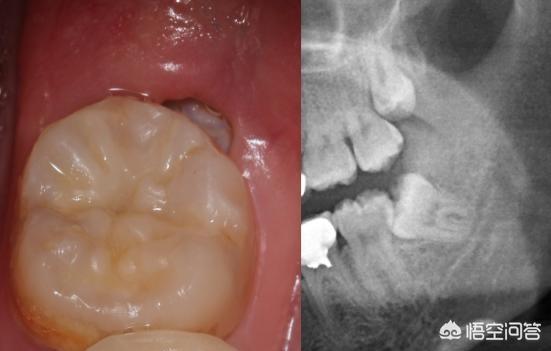

1、智齿发炎了,并且有盲袋,很明显是近中阻生,已经长歪了,和邻牙有缝隙,容易塞牙引起龋齿,在最后端清洁很难,基本这里是细菌天堂,会拖累到隔壁邻牙,大多两颗都会烂掉。